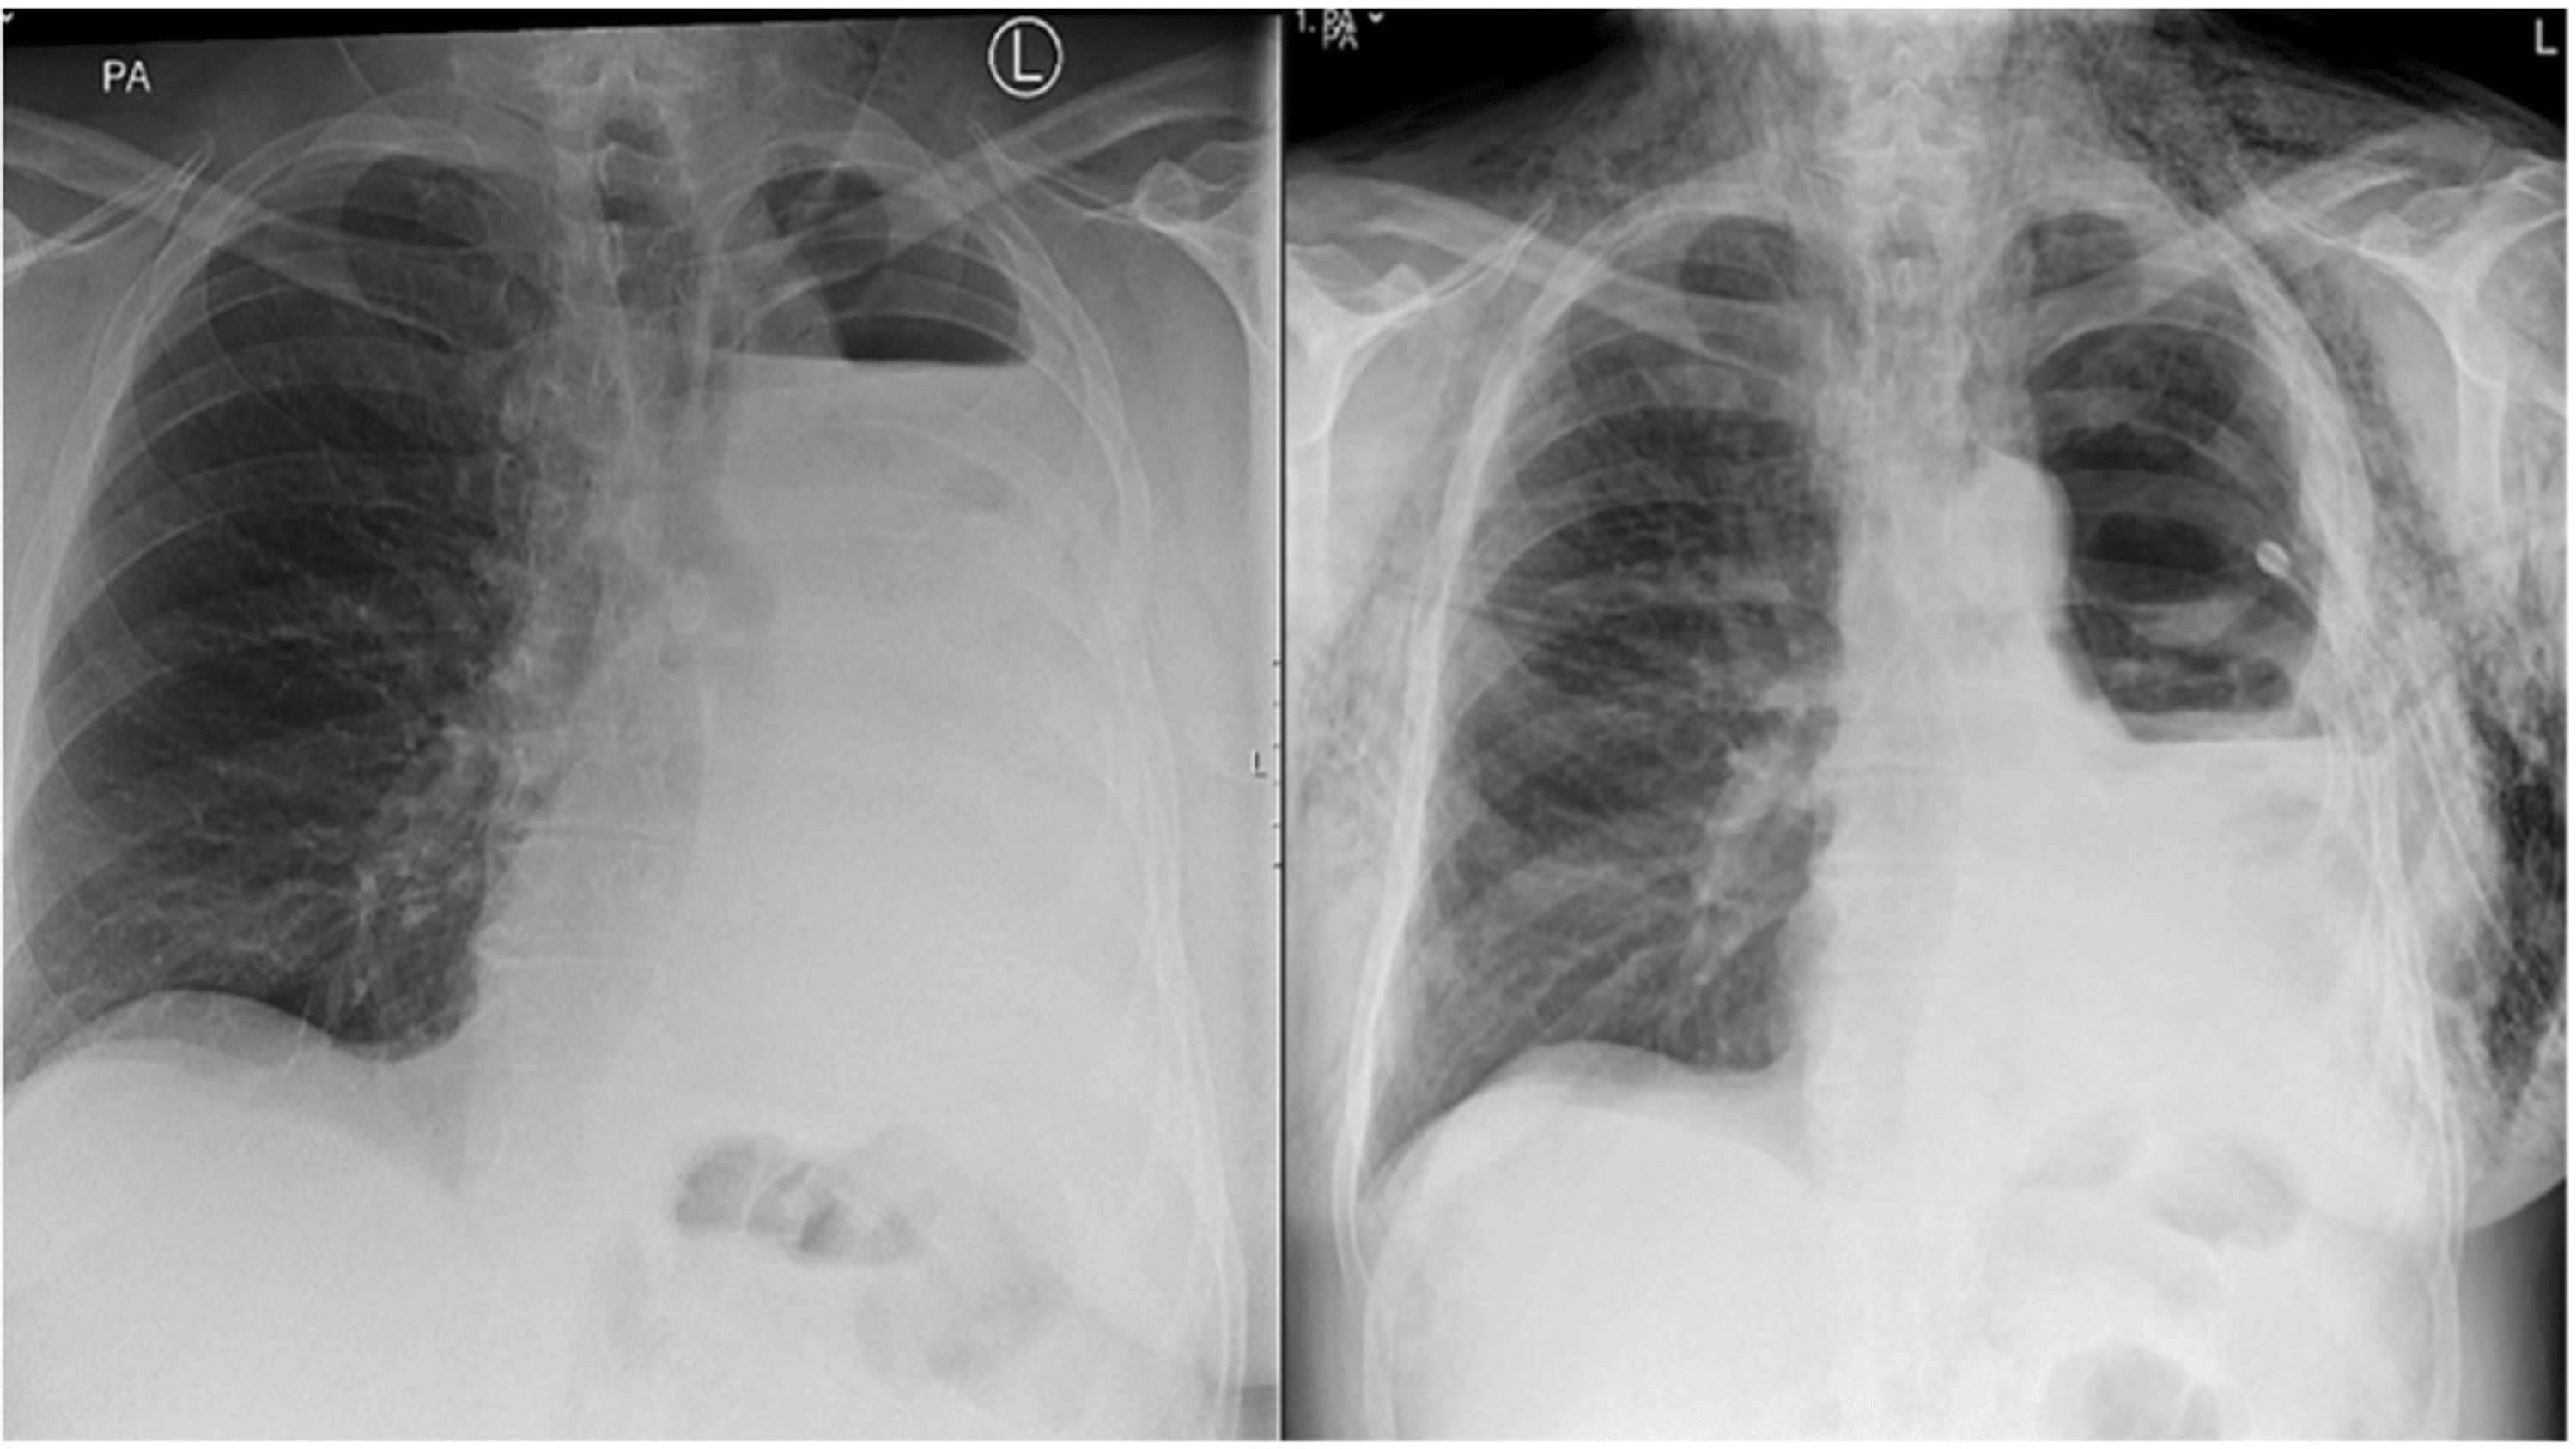

From learningradiology.com

LearningRadiology postpneumonectomy, lung, resection, removal Sleeve Pneumonectomy Definition Sleeve resections are preferred over pneumonectomy for the preservation of pulmonary function, provided a complete (r0) resection can be achieved. Sometimes the tumor has affected the chest wall or. Standard sleeve resection refers to the circumferential removal of a segment of the main bronchus in continuity with a lobectomy in. Even when the tumors involve not only the airway but. Sleeve Pneumonectomy Definition.